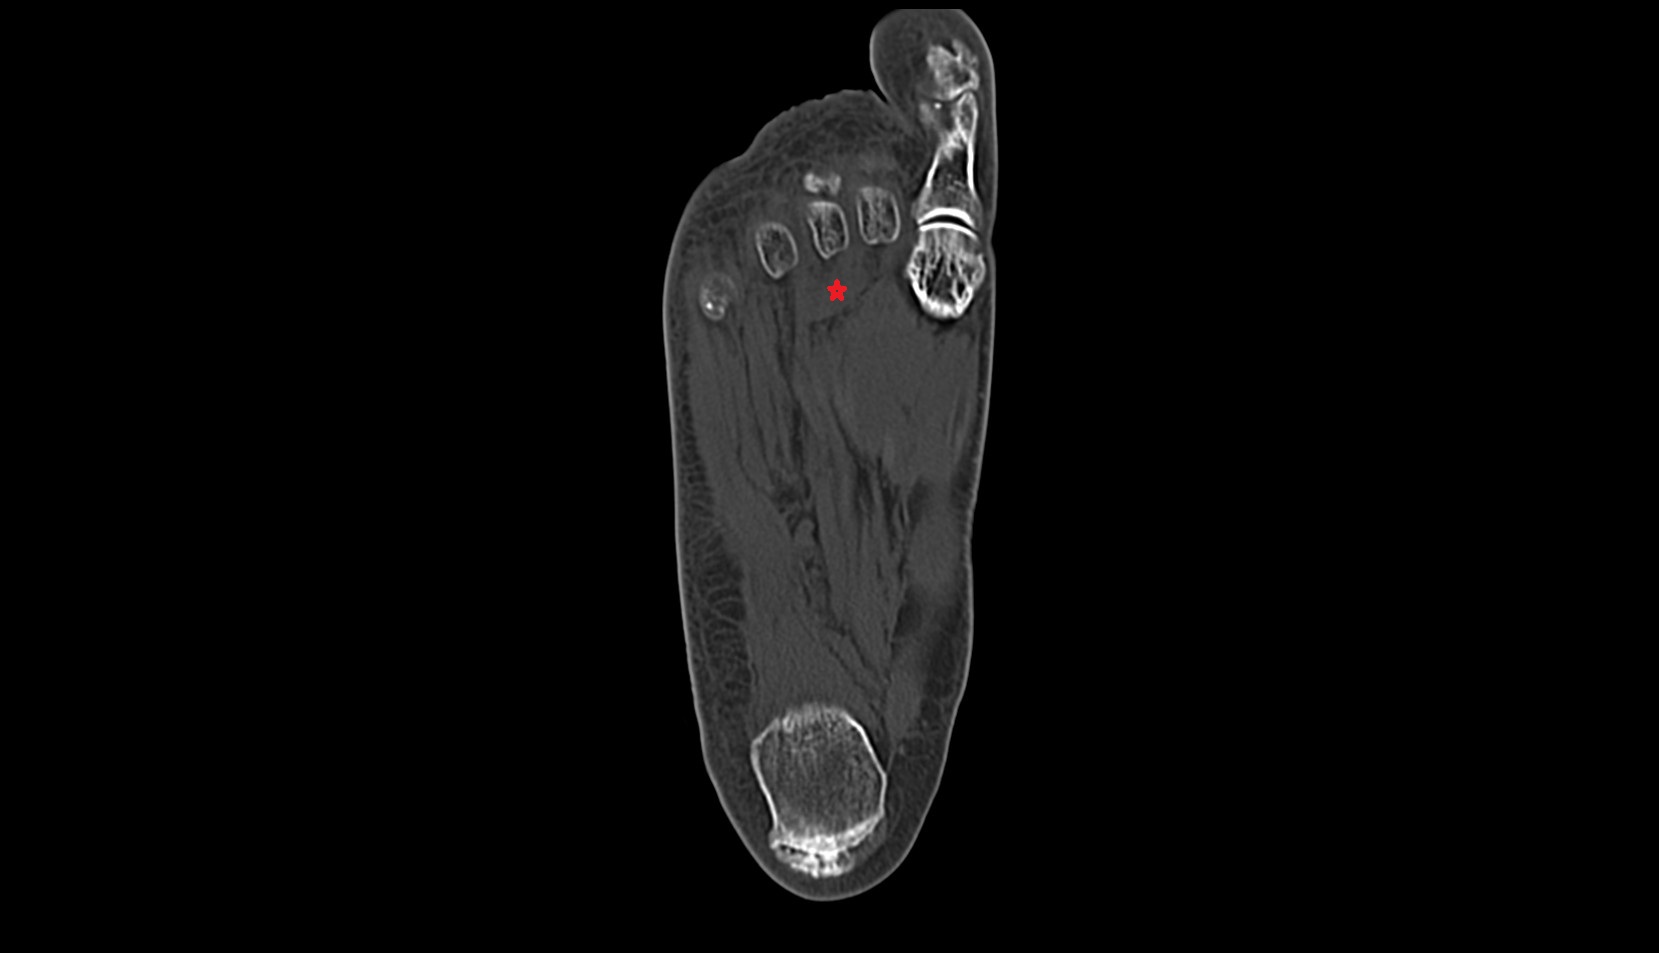

- Plantar aponeurosis